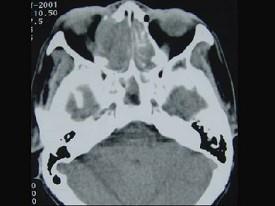

问题 女性,53岁,右侧鼻腔流血近一年,近来头痛,行CT检查如图所示,请选择正确的答案 ( )

选项 A、鼻腔炎性假瘤 B、鼻腔内血管瘤 C、鼻腔内息肉 D、副鼻窦炎 E、鼻腔癌

答案 E